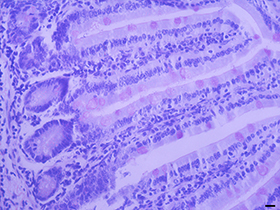

过碘酸—雪夫染色

过碘酸-雪夫(Pexiodic acid-schiff,PAS)染色又称糖原染色。胞浆内存在的糖原或多糖类物质(如黏多糖、黏蛋白、糖蛋白、糖酯等)中的乙二醇基(CHOH-CHOH)经过碘酸(Periodic acid)氧化,转变为二醛基(CHO-CHO),与雪夫(Schiff